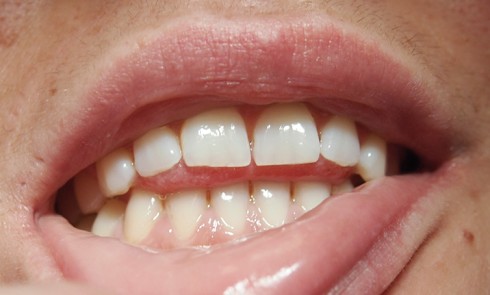

Article réservé à nos abonnés Protocole de mise en charge en 36 heures chez l’édenté total

De nos jours il est presque inconcevable de proposer un traitement implantaire au patient en voie d’édentement au maxillaire sans...